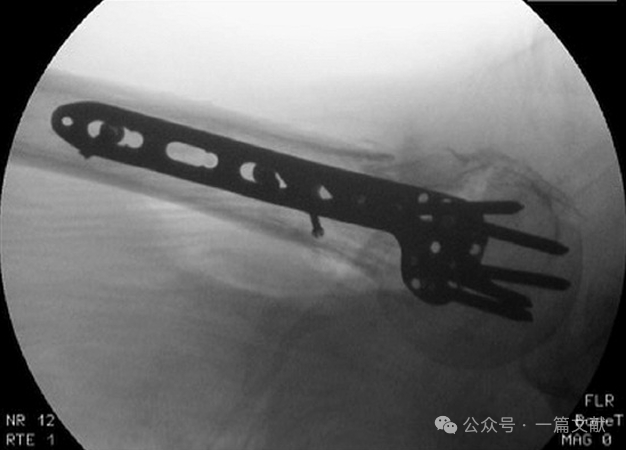

六,其他:术中C臂机也可从对侧拍摄,如下图:

术中患者体位也可采取沙滩椅卧位,具体根据情况而定。本文展示的均为仰卧位拍摄。